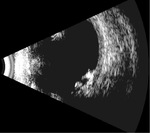

Rycina 2. Tylne odłączenie ciała szklistego bez istotnego pogrubienia kory ciała szklistego, powstałe na skutek niedawno przebytego urazu tępego. Siatkówka i naczyniówka są przyłożone

Rycina 6. Odwarstwienie siatkówki oraz wylew krwi do ciała szklistego na skutek niedawno przebytego urazu tępego

Rycina 8. Stan po zapaleniu wewnątrzgałkowym. Widoczne odwarstwienie siatkówki i odłączenie naczyniówki. Gałka oczna ze znaczną hipotonią

Rycina 9. Stan po opasaniu gałki ocznej wykonanym jako leczenie pourazowego odwarstwienia siatkówki. Widoczny wał opasania oraz liczne hiperechogeniczne zagęszczenia ciała szklistego, siatkówka jest przyłożona